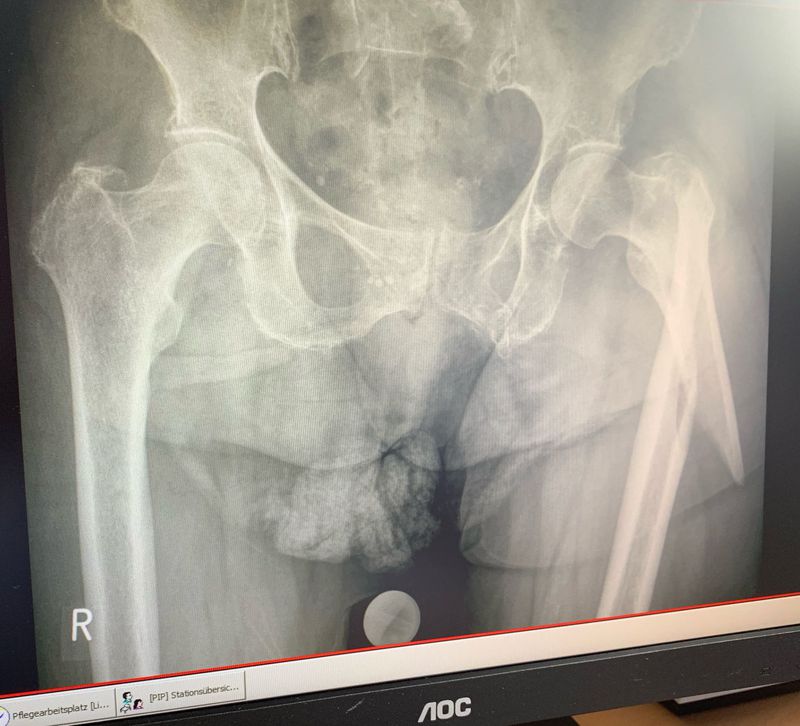

Fracture femuralis

This Patient came to the hospital with an beautiful Femuralis fracture of the left leg. This patient fell down a Stair and felt big pain in the right thighs.

Left ! Lol